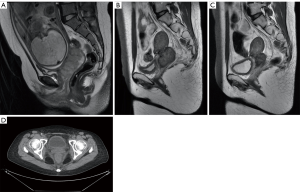

A 23-year-old patient, G1P0, presented with irregular bleeding at 9 weeks and there was no significant improvement of bleeding after progesterone treatment. Cytology results showed atypical squamous cells, while a high-grade lesion (ASC-H) could not be excluded. A large friable tumor of about 5×7 cm2 was found in her cervix and contacted bleeding. The vault had disappeared, and the left main ligament was thickened and shortened, as observed on pelvic examination at 22 weeks and 5 days of pregnancy. Squamous cell carcinoma was diagnosed by biopsy. Magnetic resonance imaging (MRI) showed an irregular mass of 7.3×2.8 cm2 on the left lateral wall of the cervix, involving left parametrial and posterior fornix close to the anterior wall of the rectum (stage IIB).

The patient had a desire to preserve the pregnancy and two cycles of TC (cisplatin and paclitaxel) regimen was indicated at the 23rd week and the 27th week of gestation. Despite this, the tumor reduction effect was not significant. A BVP (Bleomycin, Vincristine, Cisplatin) protocol, administered intravenously, at the 32nd week was indicated. A cesarean section was conducted at the 35th week of her gestation due to tumor growth and its insensitivity to NACT. The newborn weighed 2.17 kg, with Apgar scores of 10/10. The platinum level of the baby’s umbilical blood was 0.0075 µg/g. Breastfeeding was not adopted after the birth. BIP (Bleomycin, Ifosfamide, and Oxaliplatin) was intravenously injected into the patient 2 weeks after delivery.

As the tumor growth was not under control (Figure 2), the patient was treated with CCRT, external pelvic irradiation (IMRT): PTV: 45 Gy/25 f/38 d, CTV-parametrial: 56 Gy/25 f/38 d, GTV-tumor volume 1 cm inward: 56 Gy/25 f/38 d, and intracavitary brachytherapy: CTV-D90: 20 Gy/5 f/44 d, CTV-A left: 28 Gy/5 f/44 d, CTV-A right: 17 Gy/5 f/44 d. Radiotherapy completed within 58 days with 6 weeks of cisplatin. After that, arterial intervention with cisplatin was conducted 4 times combined with TC chemotherapy, simultaneously. The patient received gynecological examination at follow-up (41 months post-delivery) and no tumor lesion or recurrence was found. The child was found to be in good condition during the follow-up health check (general, cardiac and cognitive or development). Colposcopy views (Figure 3), MRI, and PET-CT (Figure 2) were observed during the treatment.